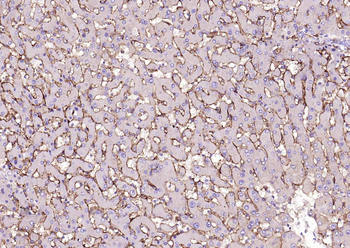

50 μl, 100 μl, 25 μl - CD14 Recombinant Rabbit Monoclonal Antibody [orb608064]Featured

IF, IHC-Fr, IHC-P, WB

Human

Rabbit

Recombinant

Unconjugated

100 μl, 50 μl, 25 μl - Rad51 Recombinant Rabbit Monoclonal Antibody [orb608069]Featured